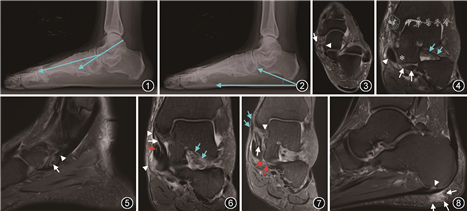

足负重X线摄影是诊断AAFD的金标准,包括前后位、侧位、Saltzman位、后足轴位等。在足负重前后位片上可进行各种角度和参数的测量来评估距骨头的覆盖情况,包括距骨-第1跖骨角(距骨长轴和第1跖骨长轴之间的夹角,正常为0~20°)、距舟关节覆盖角(距骨内外侧关节面连线与舟骨内外侧关节面连线之间的夹角,正常<7°)、距舟关节未覆盖百分比(距骨头未被舟骨覆盖的弧形区域,正常为10°~30°)以及外侧不一致角(距骨和舟骨外侧关节面的连线与距骨外侧关节面和距骨颈最窄处连线之间的夹角,正常为5°±26°)[7],其中距骨-第1跖骨角被认为是评价AAFD最有意义的指标。

在足负重侧位片上测量内侧纵弓高度、外侧纵弓高度、距骨-第1跖骨角(Meary角即距骨长轴与第1跖骨长轴之间的夹角,正常为0±4°)和跟骨倾斜度(跟骨最底部的连线与水平面的夹角,通常<20°即可认定为扁平足)(图1,2),有助于判断内侧足弓的塌陷情况并定位畸形发生的部位,如距舟关节的畸形、舟骨或第1跗中关节的异常等[7]。

MRI是显示PTT的有效影像方法,横断面显示为卵圆形低信号影,直径7~11 mm[11]。PTT腱鞘炎表现为沿PTT边缘走行的条片状液体信号,邻近软组织肿胀。PTT肌腱炎表现为肌腱增粗、形态不规则,T2信号不均匀增高。既往研究显示,MRI诊断PTT肌腱炎的灵敏度为88%,特异度为100%[12]。PTT肌腱炎可引起Meary角和跟骨倾斜角不同程度的改变,当PTT断裂时,Meary角和跟骨倾斜角将超出正常范围。PTT损伤可分为3级:1级为部分撕裂,肌腱增粗、不规则,内部出现T2高信号影,周围伴腱鞘炎(图3);2级为肌腱变细、萎缩,直径小于趾长屈肌腱,提示肌纤维的断裂或萎缩;3级为肌腱的完全撕裂,断端可出现回缩。

2.弹簧韧带的损伤:弹簧韧带,也称为跟舟韧带,被认为是内侧弓的主要静态稳定结构,其重要性仅次于PTT。其与PTT和三角韧带在舟骨内侧形成软组织复合体,能防止距骨头过度下移。弹簧韧带由3部分组成,从内侧到外侧分别为上内侧束、内侧斜束和下纵束。上内侧束是最大和最重要的束,也是最容易损伤的束,它形成了一个吊床状结构,支持距骨头部和距舟关节[13]。弹簧韧带损伤最常见的原因是PTT功能不全,导致距骨头部反复过度下移,从而使上内侧束超负荷而损伤。74%~92%的PTT撕裂患者的弹簧韧带存在损伤[14]。临床上很难通过体检来诊断弹簧韧带的损伤,因此,MRI评估显得尤为重要。弹簧韧带所有束均能很好地在MRI图像上显示,上内侧束在冠状面和轴斜面上显示最佳,当韧带厚度>5 mm或<2 mm、韧带形态发生改变、T2信号强度增加以及韧带周围出现水肿时,可诊断为损伤[15](图4)。内侧斜束和下纵束在轴面上显示最佳,但损伤不常见。

3.副舟骨:副舟骨是足舟骨近端内侧发育的一块籽骨,2%~14%的成人存在副舟骨。副舟骨可分为3种类型:Ⅰ型是PTT中2~3 mm的籽骨,与舟骨没有任何软骨连接,Ⅱ型是与舟骨结节通过厚度1~2 mm的软骨连接;Ⅲ型是一块较大的骨性突起与舟骨结节相连。大多数副舟骨无明显症状,但Ⅱ型和Ⅲ型可引起中足疼痛和足外翻,较PTT退变患者出现扁平足要更年轻化。MRI可以显示副舟骨和舟骨的骨髓水肿、骨囊肿、软骨结合处的液体以及可能出现的滑囊炎。PTT主要附着于副舟骨而不是较远的舟骨,附着端T2信号增高,副舟骨的存在会改变PTT的力学性质[16](图5)。

4.跗骨窦综合征:跗骨窦是位于距下后关节前方、距骨和跟骨之间的一个充满脂肪的圆锥管。它包含距跟韧带、颈韧带等,起到稳定距下关节的作用。AAFD足跟外翻可引起距下关节旋转和平移,使跗骨窦韧带超负荷,引起韧带的损伤,出现足部外侧疼痛、负重时后足不稳定,称为跗骨窦综合征。在MRI上跗骨窦内脂肪信号改变、结构紊乱、韧带损伤是跗窦综合征的特征表现[17](图6)。

5.三角韧带的损伤:三角肌韧带起源于内踝,由深、浅两层组成,深层主要包括前胫距韧带和后胫距韧带,它们通过抵抗踝关节外翻来稳定胫距关节;浅层包括横跨距舟关节的胫舟韧带、胫骨弹簧韧带以及横跨距下关节的胫跟韧带,胫舟韧带和胫骨弹簧韧带通过限制后足外翻和距骨头内移来稳定距舟关节[18]。以上三角韧带的损伤均与AAFD相关。深层三角韧带的损伤多发生在AAFD后期,可导致胫距关节外翻倾斜,后足外翻畸形加重。MRI是评估三角韧带损伤的首选影像学检查方法,轴面和冠状面显示最佳,正常韧带表现为均匀低信号。当韧带信号不均匀增高、形态扭曲时,可诊断其发生了变性、部分撕裂或纤维化;当韧带显示不连续,断端回缩,正常韧带区域被液体信号填充,则可诊断其完全撕裂[19](图7)。

6.足底筋膜:足底筋膜是重要的支持结构,防止足底延长以及支撑足弓。跗骨与足底筋膜在侧位上构成一个三角形结构,足底筋膜是这个三角形结构的“拉杆”,当足趾背伸、足跟升高时,足底筋膜会拉紧,从而牵引足跟和跖骨头,缩短足底并抬高足弓,当足底筋膜松弛时,足弓降低。部分学者认为足底筋膜是维持足弓最关键的结构,但足底筋膜异常和AAFD之间关系并不明确。足底筋膜最常见病变是退行性足底筋膜炎,MRI上表现为其跟骨附着处筋膜增厚(>4 mm)、形态不规则、信号强度不均匀增高,并伴有不同程度的筋膜周围软组织肿胀和骨髓水肿(图8)。